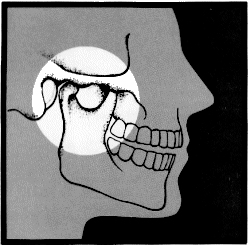

The lower jaw (mandible) is attached to the skull by a joint on each side of the face, called the temporomandibular joint. We refer to it as the TMJ. Any number of problems associated with the chewing muscles, ligaments, bones or the joints can prevent the TMJ from functioning properly. Hence, the term TMJ syndrome.

Disorders often result when chewing muscles and the TMJ work incorrectly. When this occurs, the muscles frequently cramp or go into spasm. Sometimes the spasms become part of a cycle that results in tissue damage, pain and muscle tenderness.

Accidents, including injuries to the jaw, neck, or head, or even diseases such as arthritis may cause TMJ disorders. The two most common causes of TMJ syndrome, however, are oral habits (grinding and clenching) and improper bite.

Sometimes the teeth don't come together properly when you bite. The general term for this is "malocclusion." An improper bite may cause stress on your chewing muscles, and the TMJ syndrome prevails.